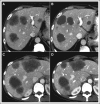

Purpose: The purposes of this study were to confirm the prognostic value of an optimal morphologic response to preoperative chemotherapy in patients undergoing chemotherapy with or without bevacizumab before resection of colorectal liver metastases (CLM) and to identify predictors of the optimal morphologic response.

Patients and methods: The study included 209 patients who underwent resection of CLM after preoperative chemotherapy with oxaliplatin- or irinotecan-based regimens with or without bevacizumab. Radiologic responses were classified as optimal or suboptimal according to the morphologic response criteria. Overall survival (OS) was determined, and prognostic factors associated with an optimal response were identified in multivariate analysis.

Results: An optimal morphologic response was observed in 47% of patients treated with bevacizumab and 12% of patients treated without bevacizumab (P < .001). The 3- and 5-year OS rates were higher in the optimal response group (82% and 74%, respectively) compared with the suboptimal response group (60% and 45%, respectively; P < .001). On multivariate analysis, suboptimal morphologic response was an independent predictor of worse OS (hazard ratio, 2.09; P = .007). Receipt of bevacizumab (odds ratio, 6.71; P < .001) and largest metastasis before chemotherapy of ≤ 3 cm (odds ratio, 2.12; P = .025) were significantly associated with optimal morphologic response. The morphologic response showed no specific correlation with conventional size-based RECIST criteria, and it was superior to RECIST in predicting major pathologic response.

Conclusion: Independent of preoperative chemotherapy regimen, optimal morphologic response is sufficiently correlated with OS to be considered a surrogate therapeutic end point for patients with CLM.